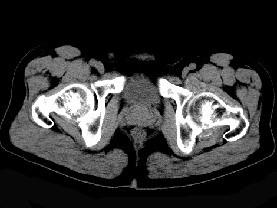

问题 男,56岁,因左髋关节疼痛、无外伤史,体检左髋关节稍肿胀,请结合所提供图像,选择最佳选项 ( )

选项 A、左髋关节滑膜炎 B、左髋关节类风湿关节炎 C、左髋关节退行性改变 D、左髋关节痛风 E、左髋关节滑膜骨软骨瘤病

答案 E